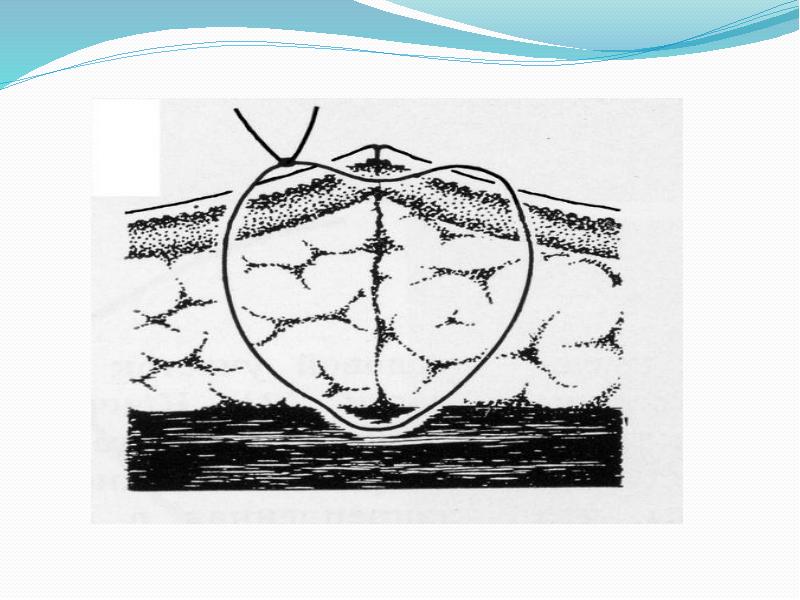

- 30. Наложение вертикального матрацного шва начинают со вкалывания иглы в кожу на

- 31. Схема проведения лигатуры при наложении вертикального матрацного шва.